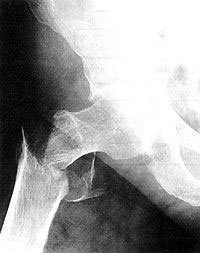

HüftbruchFolgen von Hüftbrüchen (3x häufiger als Herzinfarkt!)

40% sind gehbehindert

20% sind dauerhaft pflegebedürftig

20% sterben (nach Fisher 1991)

nach Kanis/McCloskey 1992: 25% (Kontrollgruppe 4%)

das sind genauso viele wie an Brustkrebs sterben!